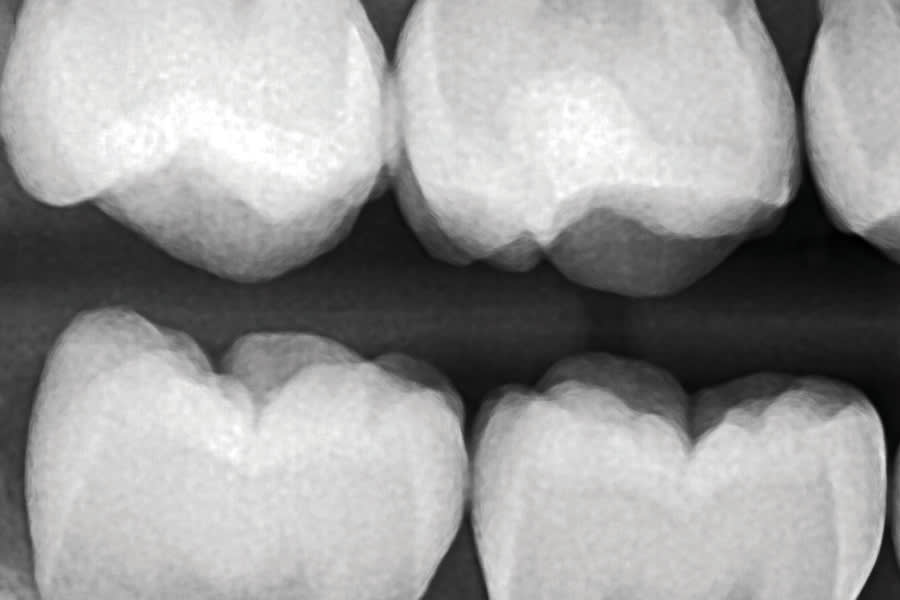

In a radiograph acquired prior to the removal of a patient's orthodontic hardware, a mid-crown radiolucency was noted on the maxillary right first molar (ie, tooth No. 3) (Figure 1). A visual examination of the crown did not indicate the presence of an obvious Class I lesion at the surface (Figure 2); however, the initial access revealed a penetrating caries lesion (Figure 3). After all of the soft carious substance was debrided, the preparation was disinfected by completing two 60-second soaks using a universal desensitizing agent with glutaraldehyde (MicroPrime™ G, Zest Dental Solutions) (Figure 4).3 Next, a round diamond bur was used to remove all of the carious dentin and establish proper retention form (Figure 5). Dentin replacement was achieved with a resin-modified calcium silicate-filled liner (TheraCal LC®, BISCO, Inc) (Figure 6). To replace the enamel, a self-etching bonding agent was applied (Adper™ Prompt™ L-Pop™, 3M) (Figure 7) followed by a bioactive resin-modified glass ionomer (RMGI) restorative material (ACTIVA™ BioACTIVE-RESTORATIVE™, PULPDENT), which was injected to overfill (Figure 8). After a curing light beam was applied for two 20-second exposures (1,200 mW/cm2) (Figure 9), a round diamond bur was used at slow speed to shape the occlusal contour (Figure 10). A final layer of the self-etching bonding agent was then applied to "glaze" the surface and improve the seal of the restoration (Figure 11), after which the occlusion was evaluated (Figure 12). The restoration was found to still be in excellent function with no signs of secondary decay or other complications at both a 2-year postoperative follow-up (Figure 13 and Figure 14) and a 5-year, 2-month postoperative follow-up (Figure 15 and Figure 16).